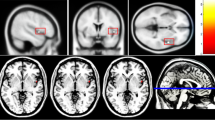

The structural images of the brain were acquired on the same 3.0 T GE Signa equipped with an eight channel phased array head coil at Hefei Fourth People’ Hospital. The T1-weighted MRI was scanned with the following parameters: repetition time = 8.5 ms; echo time = 3.2 ms; inversion time (TI) = 450 ms; flip angle (FA) = 12°; field of view (FOV) = 256 mm × 256 mm; matrix size = 256 × 256; slice thickness = 1 mm; no gaps; voxel size = 1 mm × 1 mm × 1 mm; 188 sagittal slices; and acquisition time = 296 s. During scanning, all participants were instructed to relax, remain awake with their eyes closed, and move as litter as possible. The earplugs were provided to lessen scanner noise and the sponge pads placed in the coil to minimize head movement. The MRI images of all subjects were checked by an experienced neuro-radiologist and no obvious gross abnormalities were detected. The MRIcron software was used to convert 3DT1WI into NIFIT. The same FreeSurfer software (version 5.3.0) installed in the same Ubuntu Linux version (3.2.0–29-generic) was employed to construct cerebral cortex in this study. The processing procedures produced accurate representations of the cortical surfaces through both intensity and continuity information from the entire three-dimensional MR volume in segmentation and deformation procedures. Recon-all, as one of the core commands of FreeSurfer software, was used to perform the FreeSurfer cortical reconstruction process and to calculate gray matter volume, cortical surface area and cortical thickness of right and left cerebral hemispheres in this study. According to Desikan-Kiliany-Atlas, each cerebral hemisphere was divided into 34 brain regions.

After controlling for the whole-brain gray matter volume and age, the general linear model showed significant reductions in the thickness of right bankssts and inferior parietal cortex as well as the cortical volume of left frontal pole in the patients with SCZ and violence relative to those without violence (Table 2).

In the present study, the finding of reduced whole brain volume in patients with SCZ who had a history of violence, compared to those without a history of violence, is in consistence with results of previous studies [25, 26], suggesting the possibility that certain general cognitive impairments associated with whole brain volume reduction are involved into violence. Besides, we also found abnormalities in several regions implicated in the neuropathology of violence, including left frontal pole, right bankssts and inferior parietal regions. Patients with SCZ who had a history of violent behavior displayed decreased gray matter volume in frontal pole in relation to those without violence, which is consistent with another study [27]. This indicates that changes in the prefrontal cortex including the frontal lobe might be involved in the pathophysiology of violent behavior. The prefrontal cortex is thought to play an important role in executive functioning capacity, including regulation of inhibition, emotions and movement. Damage or dysfunction of this area may interrupt the sending of inhibitory inputs to the limbic system, which is composed of hippocampus and parahippocampal gyrus and increases the risk of unregulated behavior [28], speculating that the region can be regarded as structural markers for violence [29]. Temporal lobe is implicated in emotional processing and its abnormalities are linked to the onset of psychosis, hallucinations and delusions in SCZ [30, 31]. Delusions as one of the important features of SCZ have been most consistently related to violent behavior [32]. In addition, the relation of abnormal temporal lobe with violence is also supported by other evidence that alternations in this region can lead to impaired aggression control and increased impulsivity which belong to aspects of characteristic antisocial personality disorder [30, 33]. We also found SCZ subjects with a history of violence displayed decreased cortex thickness in right parietal lobe as a part of the default-mode network (DMN) which is responsible for self-referential and reflective activity as well as attending to internal and external stimuli in relation to those without violence, in consistent with findings from the previous studies [34, 35]. Taken together, the structure volume of the brain is closely associated with the size, density and arrangement of neurons, and its change may lead to the destruction of circuits in relevant brain regions [35], suggesting abnormal neurodevelopment is vital to the neurobiology of violence in schizophrenia.